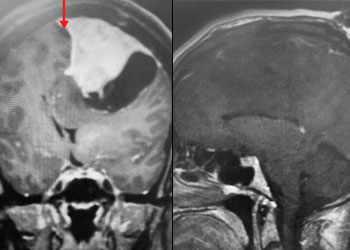

Fig 1. A) Pre-operative, post-contrast, coronal MRI. Arrow points to tumor involvement in the superior sagittal sinus. Cystic Meningiomas: Sometimes meningiomas can have partly cystic (fluid) […]